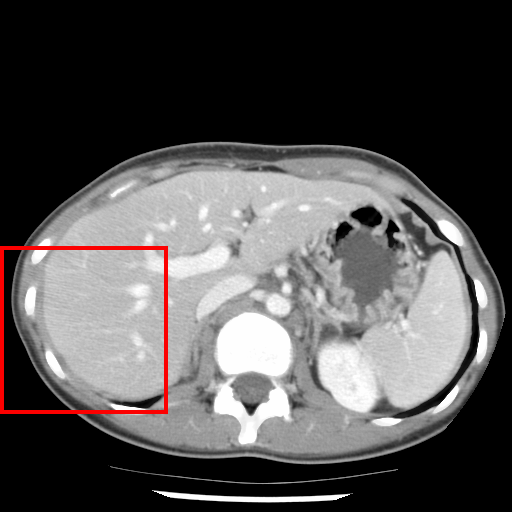

IV-A Effectiveness in 2D and 3D datasets

We first measure the effectiveness of the methods in Boundary Recall (BR) (as implemented in [1]) and Undersegmentation Error (UE) (as implemented in [19]) using plots with varying number of superpixels on four 2D datasets: Berkeley [50] (300 natural images), Birds [47] (50 natural images), Grabcut [51] (50 natural images), and Liver (50 CT slice images of the abdomen). The objects in Birds are fine and elongated structures and the images of the liver are grayscale.

The ISF methods are compared with five approaches from the state-of-the-art: SLIC (Simple Linear Interative Clustering) [1] 111http://ivrl.epfl.ch/supplementary_material/RK_SLICSuperpixels/, LSC (Linear Spectral Clustering) [15] 222http://jschenthu.weebly.com/projects.html, ERS (Entropy Rate Superpixel) [16], LRW (Lazy Random Walk) [17] 333https://github.com/shenjianbing/lrw14/, and Waterpixels [18]. Except for ISF-REGMIN, the remaining ISF methods are competitive among themselves with some differences in effectiveness. Therefore, in order to avoid busy and confusing plots, we present the effectiveness of two of the best ISF methods (10 iterations), ISF-GRID-ROOT and ISF-MIX-MEAN, for each dataset. We maintain ISF-REGMIN in the plots, because it (a) uses an integer path cost function, which allows fast computation in time proportional to the number of pixels and independent of the number of seeds (superpixels), (b) does not require seed recomputation, and even being the simplest among the ISF methods, (c) it shows consistently better effectiveness than its counterpart, Waterpixels [18]. We also include a fast hybrid approach, namely SLIC-ISF, that combines 10 iterations of SLIC for seed estimation, followed by 2 iterations of ISF, to show that it is competitive with the other ISF methods in most datasets. Figures 3–6 show the results of this first round of experiments, using and for the ISF methods that use or .

Although LSC presents the best performance (the highest BR and the lowest UE) in Berkeley, the same is not observed in the other three datasets. For Birds, Grabcut, and Liver, the best methods are ISF-GRID-ROOT, ISF-GRID-ROOT (being equivalent to ISF-MIX-MEAN), and ISF-MIX-MEAN, respectively. In Berkeley, ISFMIX-MEAN performs second best in BR and SLIC-ISF performs second best in UE. ISF-REGMIN is consistenly better than Waterpixels in both BR and UE for all datasets. ERS performs well in Berkeley, but its performance is not competitive in the other three datasets. Although SLIC is the fastest and most used method, its performance is far from being competitive in all datasets. Among the baselines, LSC is the most competitive with the ISF methods. However, it seems that the performance of LSC in UE can be negatively affected for thin and elongated objects, such as birds. Except for Berkeley, SLIC-ISF presents better performance than ERS in BR and UE.

In conclusion, one cannot say that there is a winner for all datasets, but it is clear that ISF can produce highly effective methods with different performances depending on the dataset. In Birds, Grabcut, and Liver, ISF shows better effectiveness than the most competitive baseline, LSC. This shows the importance of obtaining connected superpixels with no need for post-processing. The performance of LSC in UE is usually inferior when compared to its performance in BR. Birds dataset is clearly a case in the point. Indeed, LSC produces less regular superpixels with high BR. In sky image segmentation, as we will see, this property of LSC considerably impairs its effectiveness. Between ISF-GRID-ROOT and ISF-MIX-MEAN, we can say that ISF-MIX-MEAN provides better results in most datasets, including the application of sky image segmentation. We believe this is related to the advantages in effectiveness of mix sampling over grid sampling. Figure 7 then illustrates the quality of the segmentation in images from three datasets using the best ISF method for the dataset, the fastest approach, SLIC, and the most competitive baseline, LSC. Additionaly, we show the ISF method with a choice of that produces more regular superpixels without compromising its performance in BR and UE. This simply shows that by choice of , ISF can control superpixel regularity.